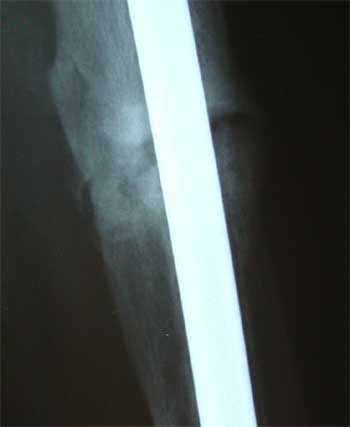

Jan. 4, 2005 X-ray update

Anterior view of x-rays. Week 6 post op, Nov. 16, on left. 3 months (current) on the right.